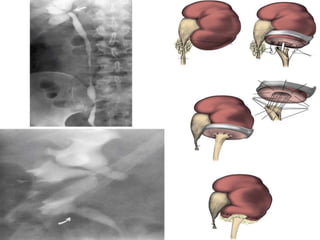

OPEN PYELOPLASTY

– Gold Standard.

– Dismembered pyeloplasty is the most common

(Anderson Hynes ).

Advantages:

-This approach can be used regardless of whether the ureteral insertion is

high on

the pelvis or already dependent.

-It also permits reduction of a redundant pelvis or straightening of a tortuous

proximal ureter.

-anterior or posterior transposition of the UPJ can be achieved when the

obstruction is due to accessory or aberrant lower pole vessels.

-only a dismembered pyeloplasty allows complete excision of the

anatomically or functionally abnormal UPJ itself.

Disadvantages:

Dismembered pyeloplasty is not well suited to UPJ obstruction associated

with lengthy or multiple proximal ureteral strictures or to patients in whom

the UPJ obstruction is associated with a small intrarenal

pelvis.

OPEN PYELOPLASTY – GoldStandard. – Dismembered pyeloplasty is the most common (Anderson Hynes ). Advantages: -This approach can be used regardless of whether the ureteral insertion is high on the pelvis or already dependent. -It also permits reduction of a redundant pelvis or straightening of a tortuous proximal ureter. -anterior or posterior transposition of the UPJ can be achieved when the obstruction is due to accessory or aberrant lower pole vessels. -only a dismembered pyeloplasty allows complete excision of the anatomically or functionally abnormal UPJ itself. Disadvantages: Dismembered pyeloplasty is not well suited to UPJ obstruction associated with lengthy or multiple proximal ureteral strictures or to patients in whom the UPJ obstruction is associated with a small intrarenal pelvis.